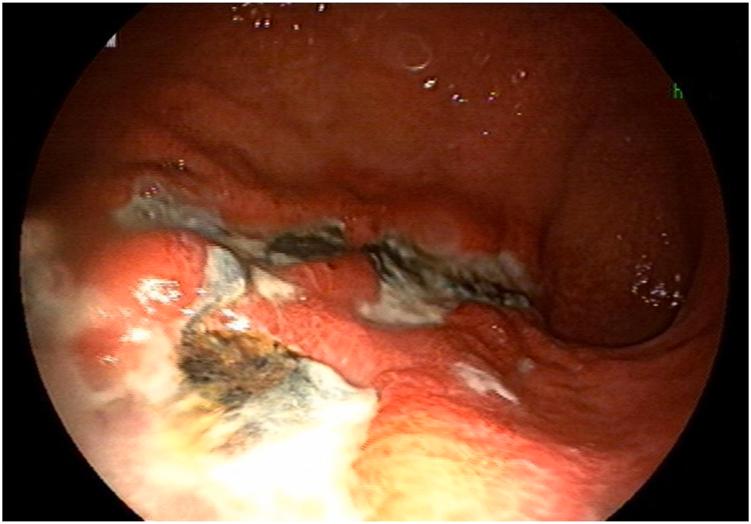

In this study, we reported a previously immunocompetent patient who developed cytomegalovirus-induced gastric ulcers after severe acute respiratory syndrome coronavirus 2 (SARS-CoV-2) infection. A 33-year-old man was referred to our center with complaints of persistent dysphagia and odynophagia, and epigastric pain and discomfort after ingesting solids or liquids, a few days after his hospital discharge following admission to treat coronavirus disease 2019 (Covid-19). Endoscopy revealed inflammation and a whitish exudate in the esophagus, and multiple large active ulcers in the stomach. Histopathological and immunohistochemical findings were strongly suggestive of cytomegalovirus infection.

在本研究中,我们报告了一名既往免疫功能正常的患者,其在感染严重急性呼吸综合征冠状病毒2(SARS-CoV-2)后出现了巨细胞病毒诱导的胃溃疡。一名33岁男性因持续吞咽困难、吞咽痛以及在摄入固体或液体后出现上腹部疼痛和不适而被转诊至我们中心,这些症状出现在他因治疗2019冠状病毒病(Covid-19)入院出院几天后。内镜检查显示食管有炎症和白色渗出物,胃内有多个大的活动性溃疡。组织病理学和免疫组织化学结果强烈提示巨细胞病毒感染。